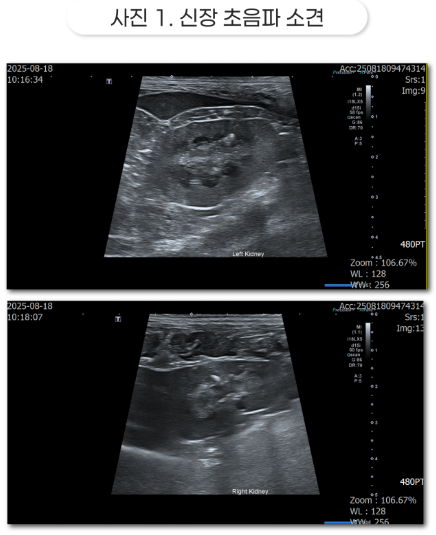

- 영상 검사: 신장을 초음파로 확인해 보니, 신장 표면이 매끄럽지 않고 울퉁불퉁하게 보였으며, 신장 안쪽에 돌처럼 굳은 물질이 일부 보였습니다. 신장의 겉 부분은 정상보다 밝게 보이고 수질과 겉질의 경계가 사라졌었습니다.